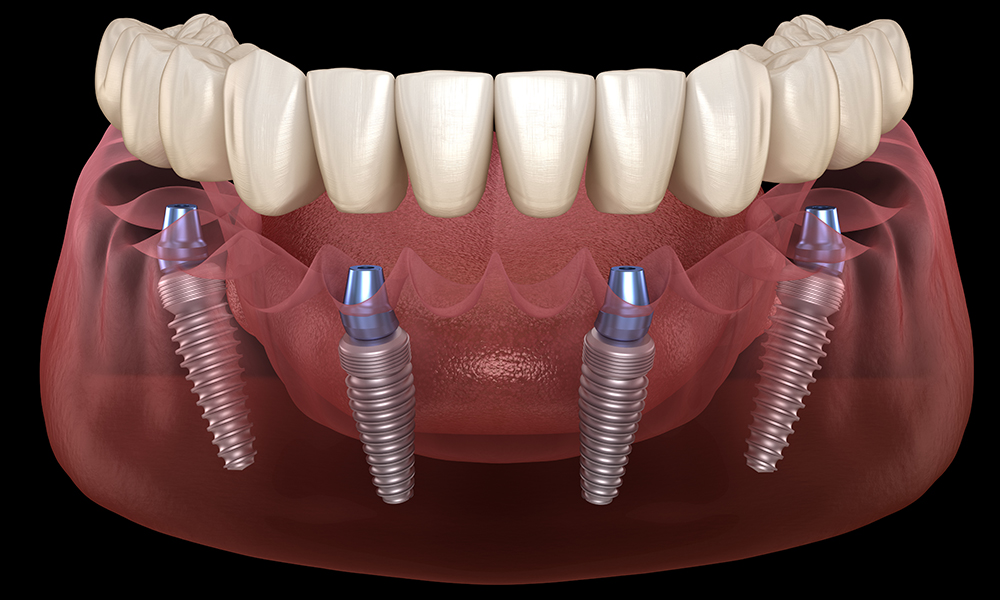

All on four nobel Biocare

El All on Four es un técnica avanzada de implantologia con amplia evidencia científica con la que somos capaces de rehabilitar de manera completamente fija casos con perdida ósea severa, sin injertos de hueso y en menos tiempo. En una sola cirugía realizamos la extracciones de los dientes infectados si existen, colocamos los cuatro implantes y tomamos las medidas para la confección de la prótesis provisional completamente fija y en solo 24 horas es colocada en la boca del paciente. Pasados 3-4 meses se procede a tomar las impresiones definitivas y colocación de la prótesis definitiva de porcelana. Esta técnica la realizamos con la marca líder en implantologia mundial Nobel Biocare. Pida cita en nuestra clínica y le ofreceremos el plan de tratamiento adecuado para su caso.